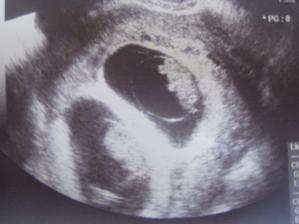

Pidižva č.2 a č.3... :o)